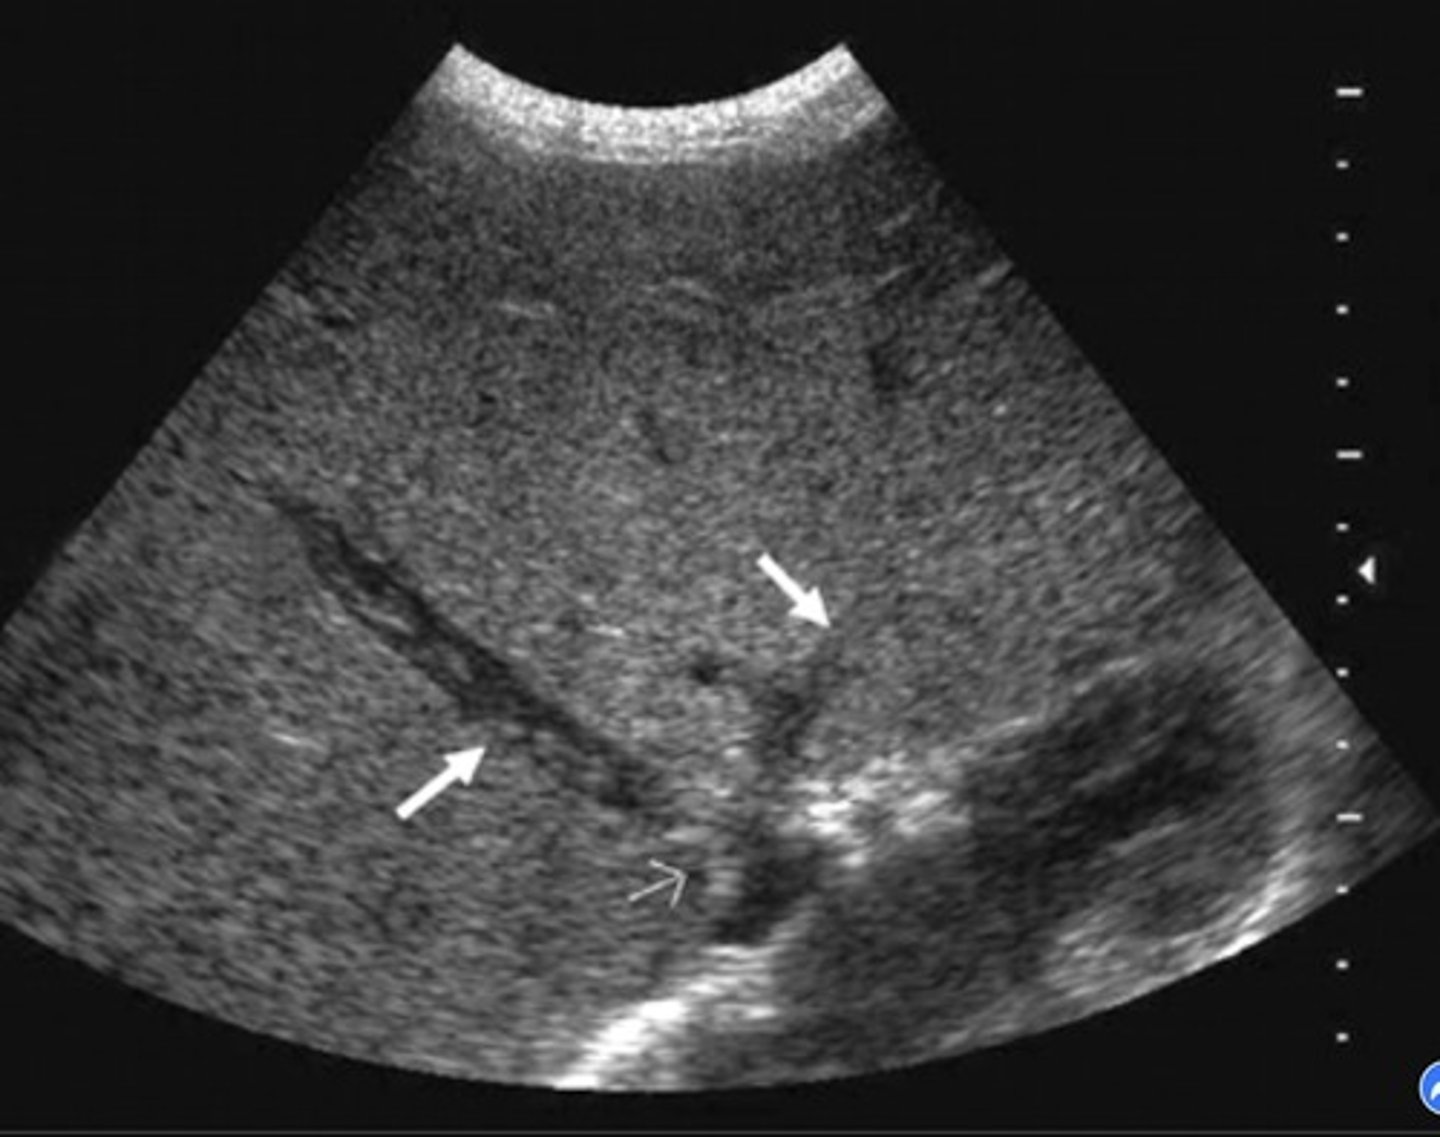

Portal HTN 2D Findings

Large pulmonary vein

Collaterals

Splenomegaly

Ascites

Enlarged hepatic artery

Cirrhosis Findings

Portalization of hepatic veins

Hepatofugal flow in portal vein & splenic vein